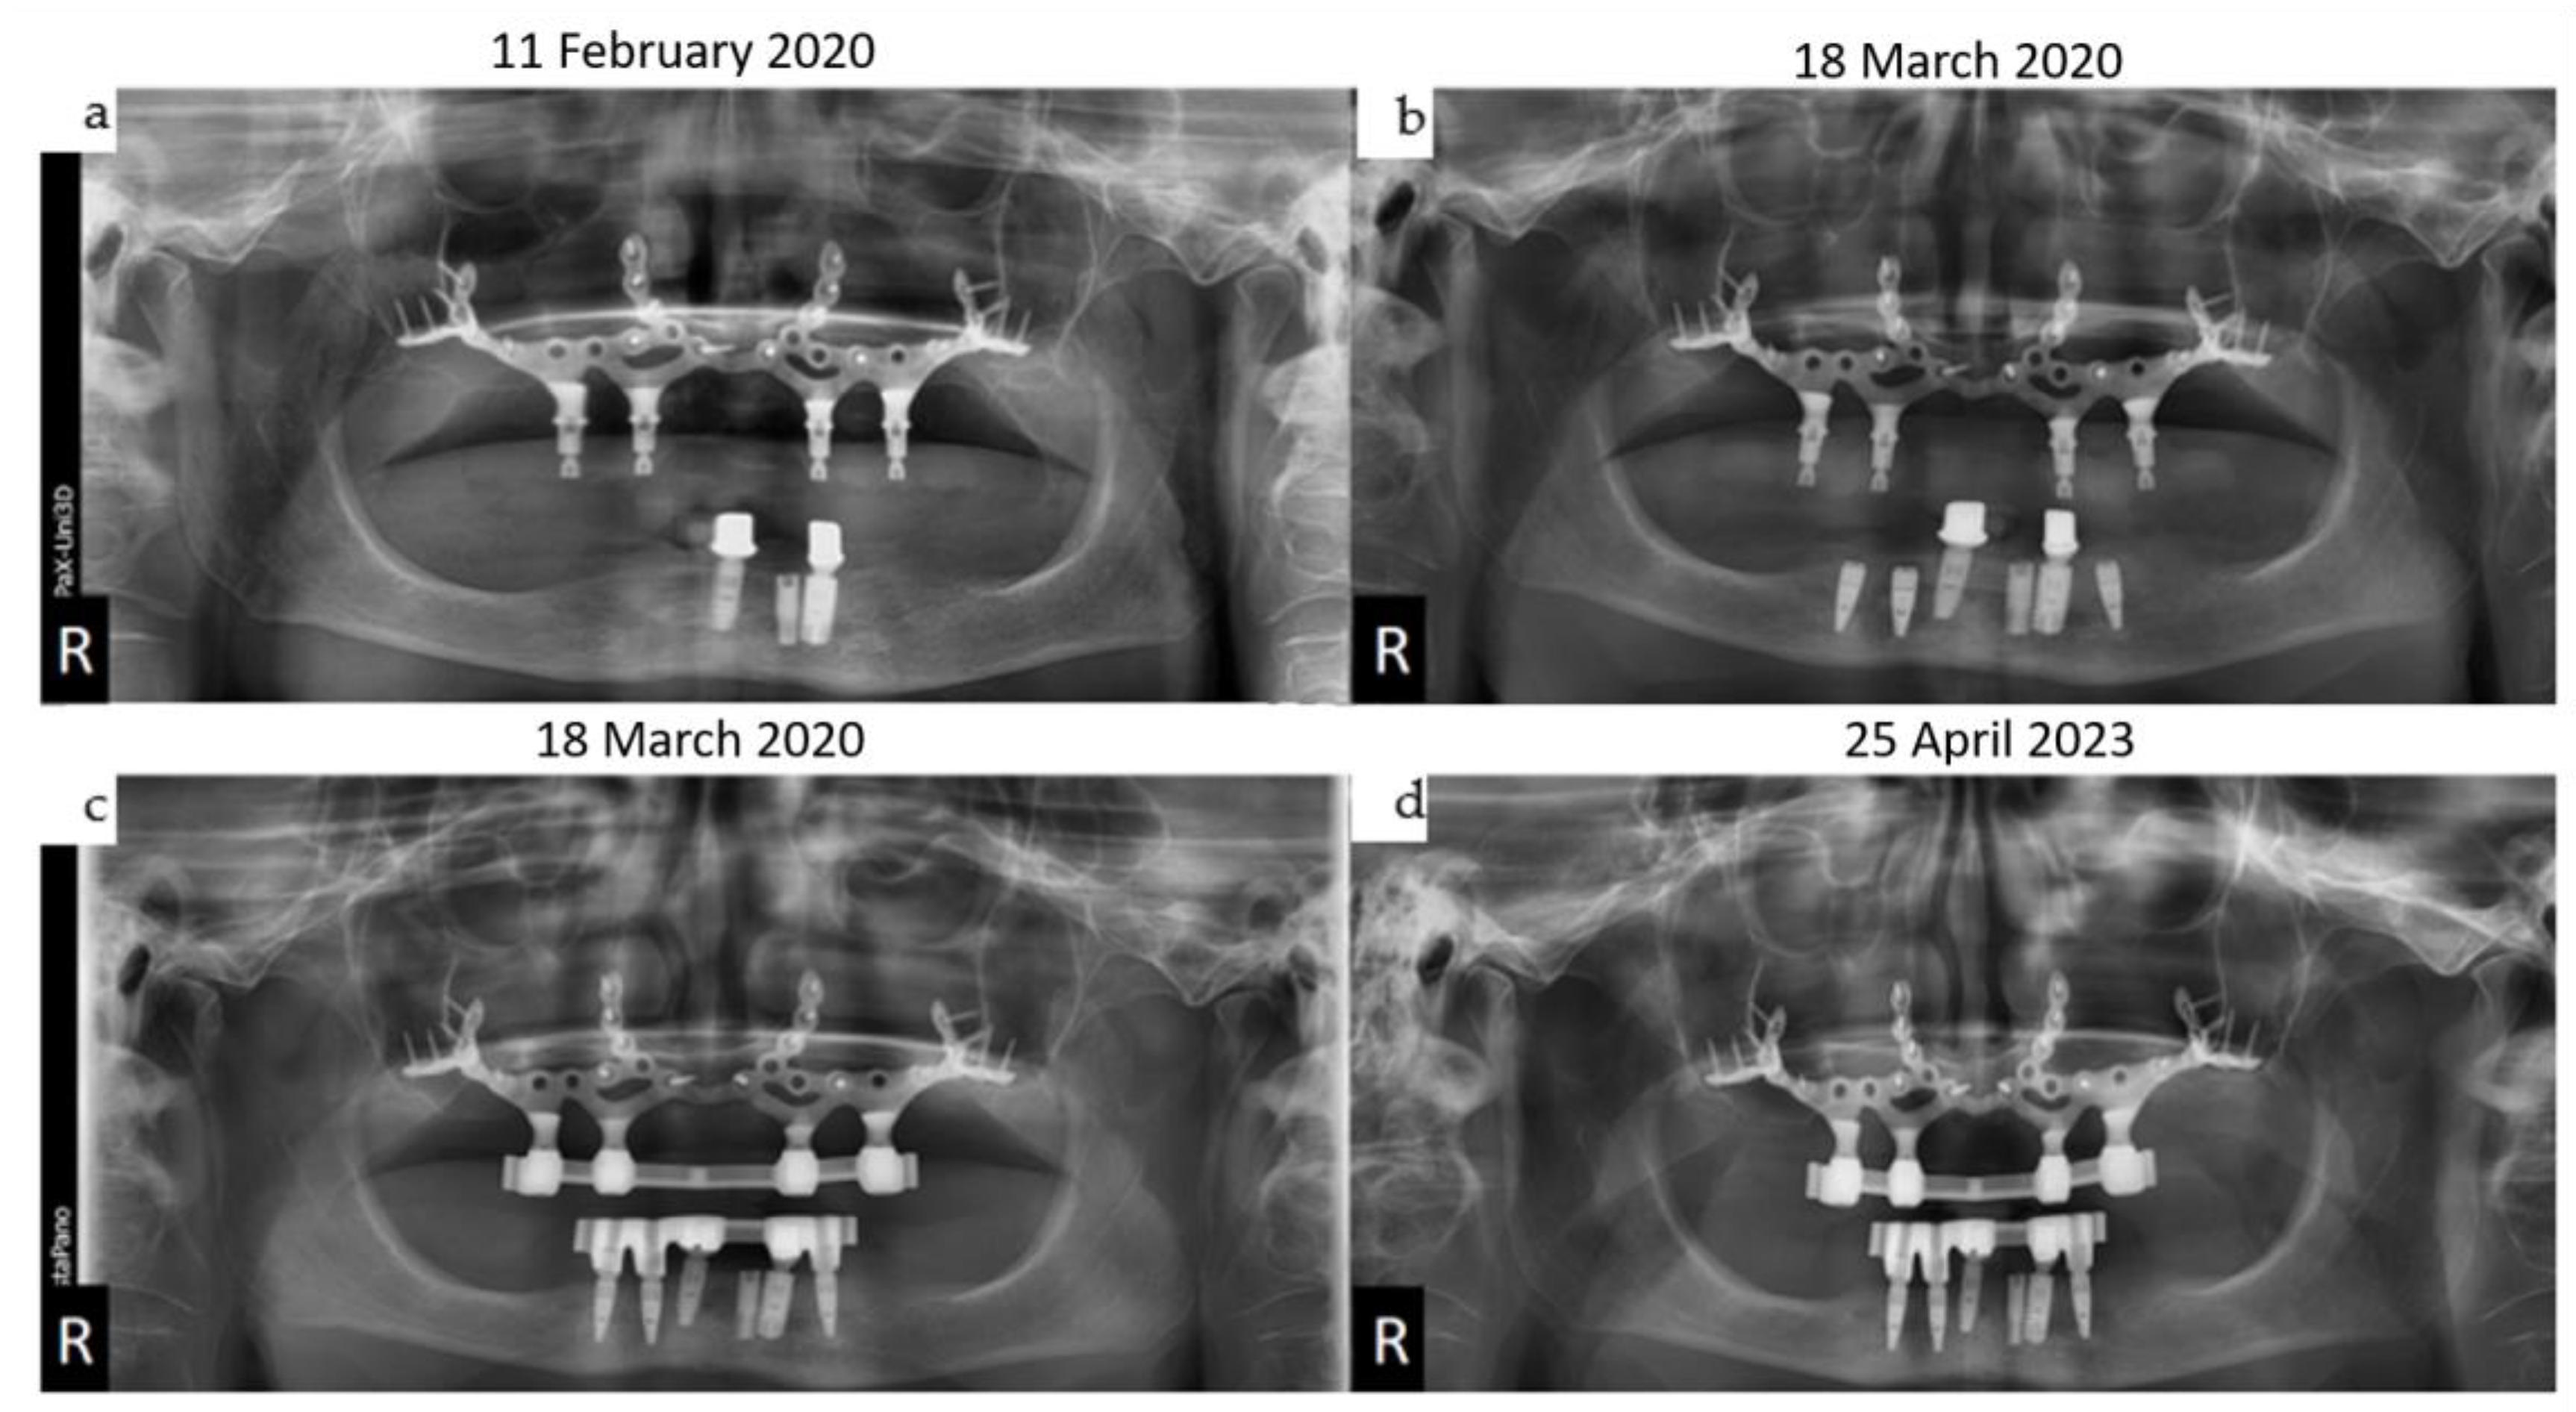

Figure 5. (ad): Four orthopantomograms depict the dental rehabilitation sequence, commencing with the insertion of the IPS Implants® Preprosthetic (KLS Martin-Group, Tuttlingen, Germany) (a); subsequently, the positions for the three bone-level tapered implants were drilled in a 3D-guided manner in a second step (b). During recall, the final bar-retained suprastructure (c) is visible, as well as at the three-year follow-up (d). No bone loss or screw loosening is evident. The key distinction between conventional implants and IPS Implants® Preprosthetic anchorage is apparent: unlike conventional implants, where anchorage relies on multivector screw-based fixation near the area equivalent to the dental implant shoulder, the IPS Implants® Preprosthetic constitutes a one-piece implant with a rotationally stable telescoping abutment component.